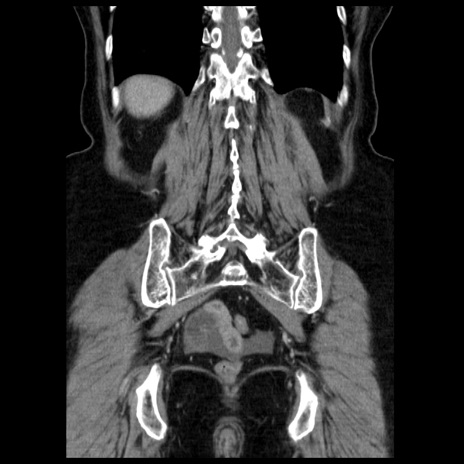

症例13(冠状断像)

【症例】70歳代女性

【主訴】腹痛、嘔吐

【現病歴】15時間程前(昨晩)より腹痛あり。今朝になっても症状の改善なく、嘔吐あり。腹痛も増悪あり、救急外来受診。

【既往歴】子宮癌全摘術後

【身体所見】意識清明、BP 121/72mmHg、P 74bpm、SpO2 100%(RA)、腹部:平坦・軟、腸雑音ほぼ聴取せず。下腹部・心窩部・臍左上に圧痛あり。反跳痛なし。

【データ】WBC 10600、CRP 0.15